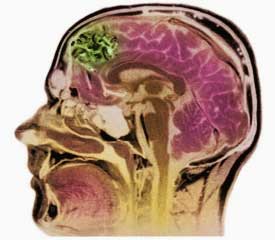

Врачи отмечают, что диагностика ангиом головного мозга, таких как кавернозные и венозные, требует комплексного подхода. На первом этапе важна магнитно-резонансная томография, которая позволяет точно визуализировать образование и оценить его размеры и расположение. Специалисты подчеркивают, что правильная интерпретация снимков играет ключевую роль в выборе метода лечения.

Лечение и диагностика ангиом головного мозга, таких как кавернозные и венозные, вызывают много обсуждений среди пациентов и специалистов. Многие люди отмечают, что ранняя диагностика играет ключевую роль в успешном лечении. Современные методы визуализации, такие как МРТ и КТ, позволяют точно определить расположение и размер ангиомы, что значительно облегчает выбор тактики лечения.

Перед тем как направить пациента на операцию, врачи проводят комплексные диагностические исследования, которые включают сбор анамнеза, ангиографию и компьютерную томографию. Если обнаруживаются каверны, то применяется МРТ-диагностика.

Для более точного планирования операции хирурги также назначают трактографию. Получив полное представление о состоянии пациента, они могут предложить один из трёх методов хирургического вмешательства: